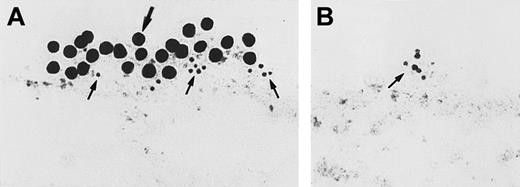

Immunoelectron microscopy for gC1qR antigen on nonpermeabilized EA.hy926 endothelial cells.

Cell suspensions were fixed with PLPG and incubated with anti-gC1qR or nonimmune mouse IgG. (A) The bound anti-gC1qR antibodies were visualized by an immunogold procedure as indicated in “Materials and methods.” Clusters of 10-nm gold particles, indicating the presence of bound anti-gC1qR, are seen segmentally on the endothelial plasma membrane. (B) Incubation of nonimmune IgG with the cells. The figure is a representative experiment of 2.

Investigations next proceeded to determine the amount of CK1 antigen expressed on HUVECs. An iodinated anti-RRY18 F(ab′)2was prepared for direct cell-binding studies (Figure4). When the iodinated F(ab′)2 was incubated with HUVECs, there was a plateau in binding at about 200 minutes (Figure 4). At that time, there was about 12 ng iodinated F(ab′)2 specifically bound per 106 HUVECs. This result calculated to be about 7.2 × 104 molecules of anti-RRY18 CK1 epitope per cell. Further investigations were performed to determine if CK1 antigen was on the membrane of HUVECs in suspension as determined by flow cytometry (Figure 5). Using flow cytometry, epitopes to CK1 were detected on HUVEC membranes using anti-GPV20 and anti-RRY184,5 (Figure 5). Additional studies were performed to determine if the other HK-binding proteins, uPAR and gC1qR, were present on HUVEC membranes. The uPAR was identified on HUVECs by flow cytometry (Figure 5). Moreover, unlike previous studies,6-8 gC1qR antigen was also expressed on the membrane of soluble HUVECs as seen on flow cytometry (Figure5). Confirmation that gC1qR antigen was expressed on the membrane of endothelial cells was performed by immunoelectron microscopy (Figure6). Using monoclonal antibody clone 74.5.2, gC1qR antigen was seen in clusters on the external membrane of EA.hy926 cells by immunoelectron microscopy using 10 nm immunogold (Figure 6).